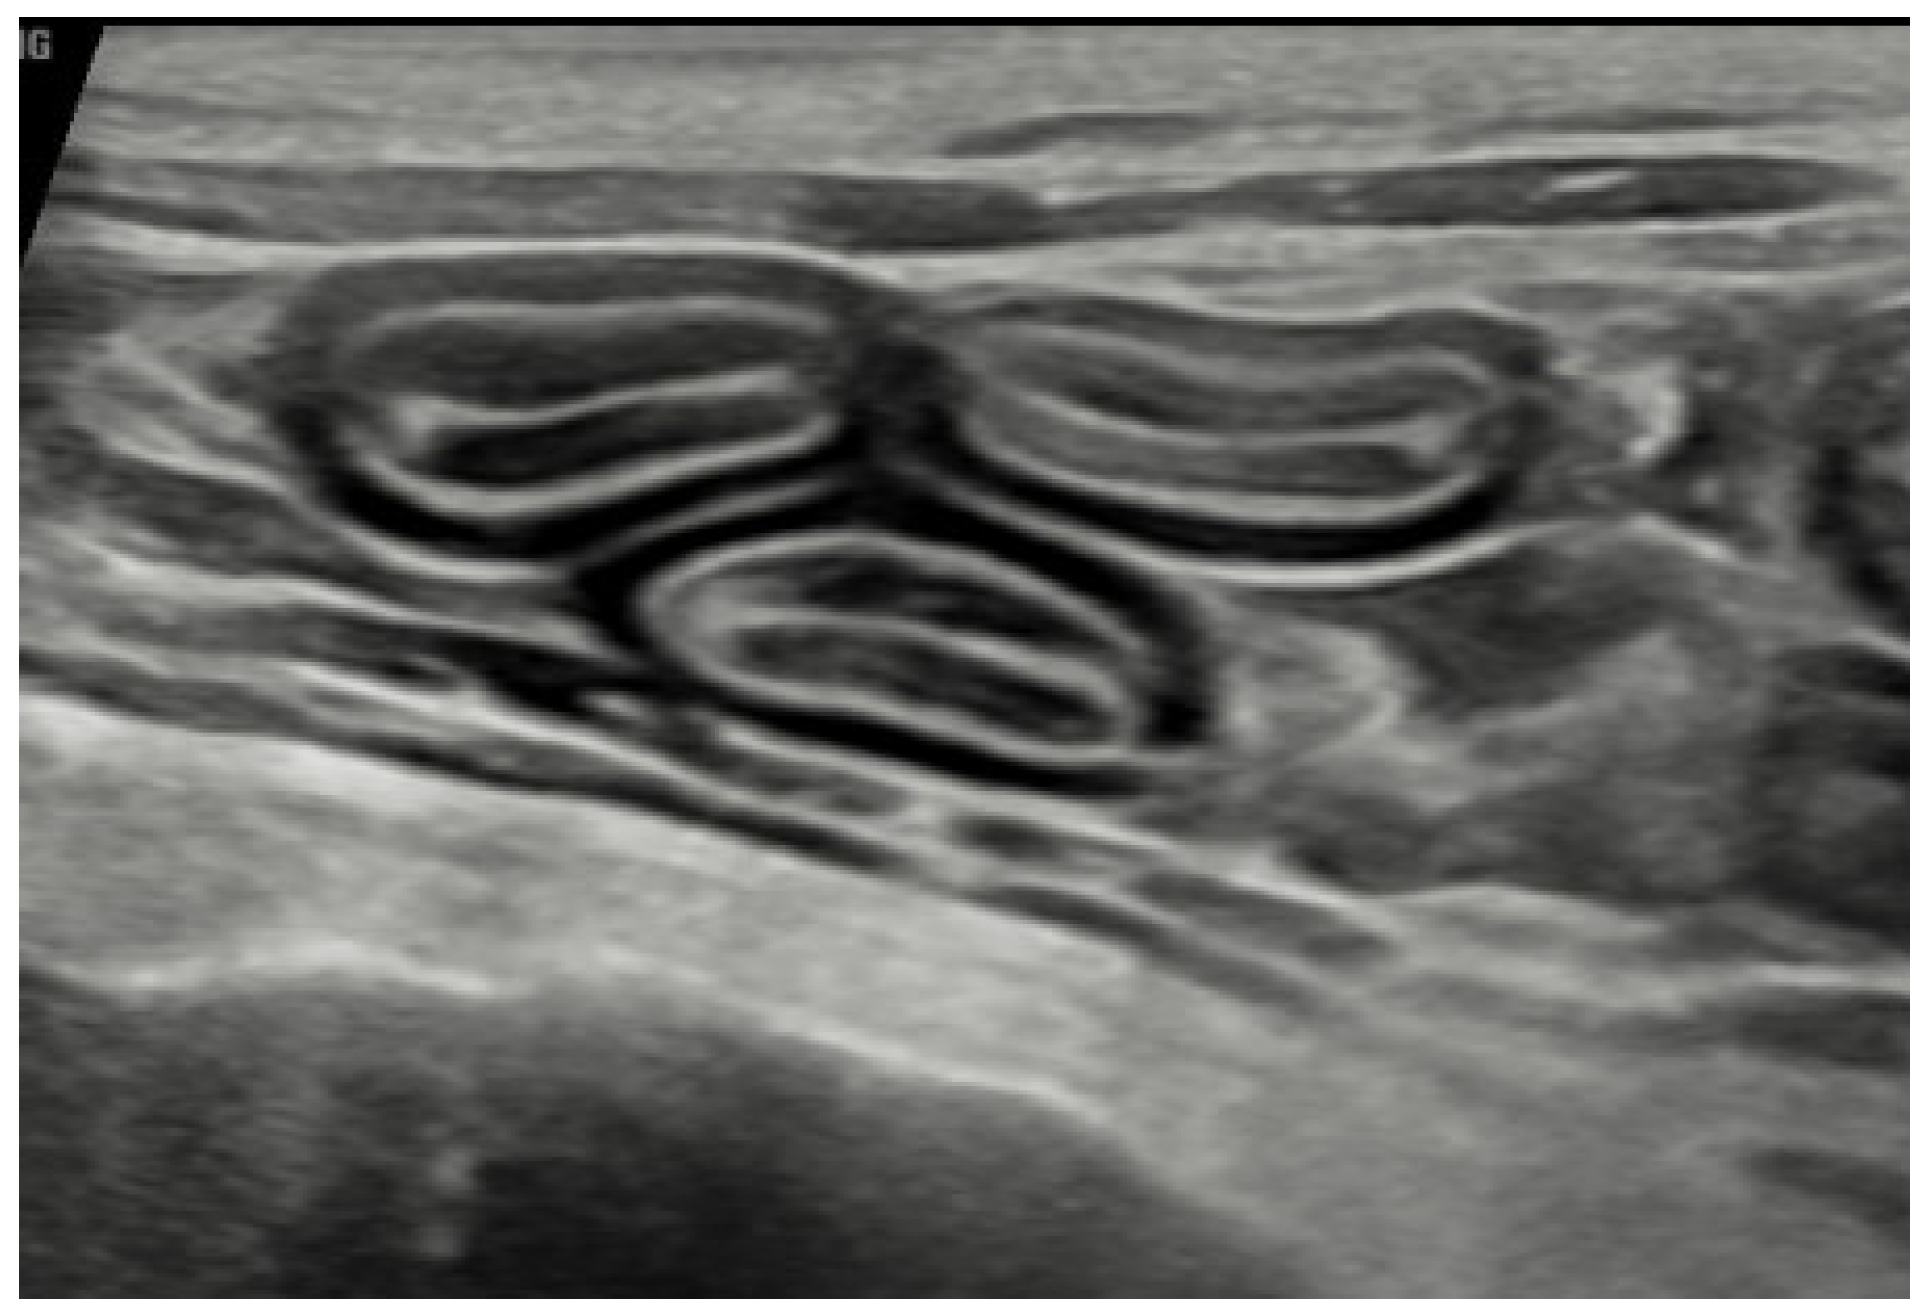

2.1. Investigation of Chronic Diarrhoea

- Daniaux, L.A.; Laurenson, M.P.; Marks, S.L.; Moore, P.F.; Taylor, S.L.; Chen, R.X.; Zwingenberger, A.L. Ultrasonographic thickening of the muscularis propria in feline small intestinal small cell T-cell lymphoma and inflammatory bowel disease. J. Feline Med. Surg. 2014, 16, 89–98. [Google Scholar] [CrossRef] [PubMed]